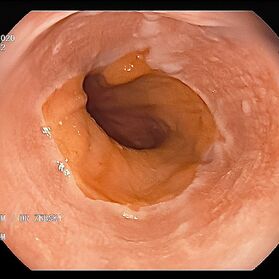

Die Gastroskopie (Magenspiegelung) hat sich als sicheres Standardverfahren zur Beurteilung des oberen Verdaungstraktes bei vielfältigen Krankheitsbildern und Fragestellungen fest etabliert.

Mit einer Gastroskopie werden Speiseröhre, Magen und Zwölfingerdarm (der oberste Teil des Dünndarms) untersucht. Dazu wird ein geschmeidig biegsames, schlankes Endoskop mit eingebauter Digitalkamera durch den Mund eingeführt. Minimalste Veränderungen können dabei gesehen werden, die im Röntgenbild oder einer Kernspintomographie (MRT) noch gar nicht erkannt werden. Im Vergleich zu anderen bildgebenden Untersuchungsverfahren ist bei der Endoskopie neben der wichtigen optischen Beurteilung auch die sofortige Möglichkeit gegeben, Gewebeproben aus auffälligen Bereichen zu entnehmen. Dazu wird eine kleine Spezialzange durch einen Kanal im Endoskop geschoben und die Probe ganz präzise aus dem entsprechenden Gewebe gewonnen. Da die Schleimhäute schmerzunempfindlich sind, spüren Sie davon nichts. Die Proben werden von Spezialisten mikroskopisch untersucht und ermöglichen dann eine zielgerichtete Therapie; zum Beispiel wenn eine Magenschleimhautentzündung durch eine chronische Infektion ausgelöst wird, die mit einer Antibiotikakur erfolgreich behandelt werden kann.